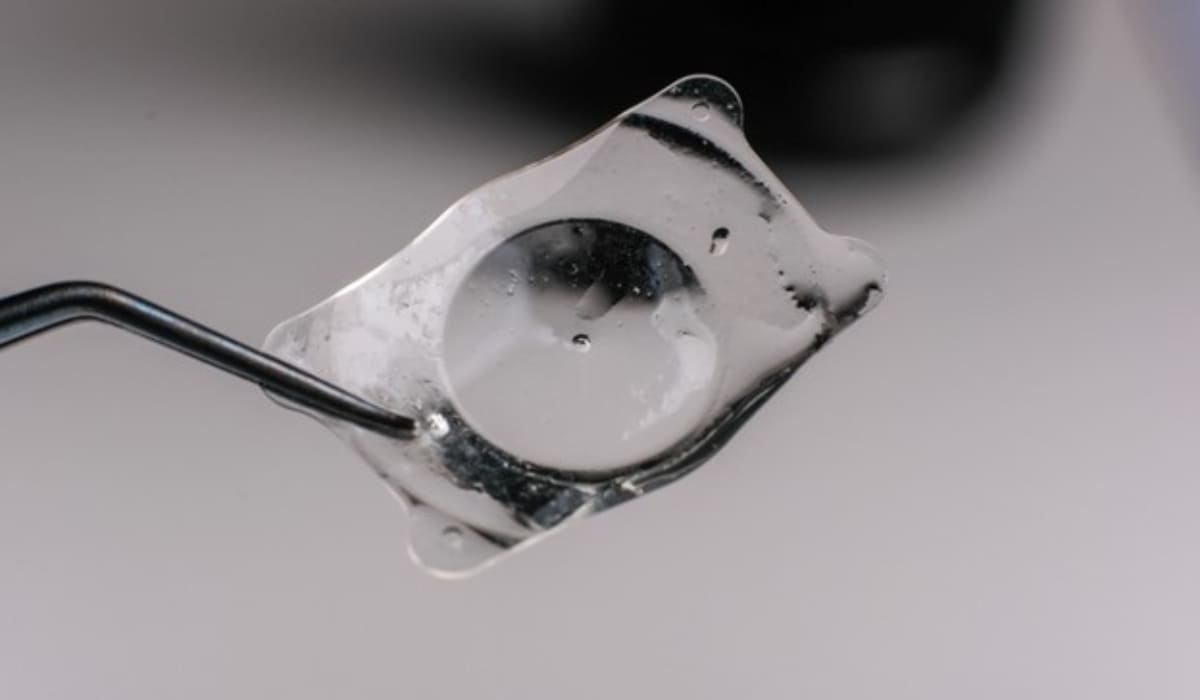

Mổ mắt Phakic là phương pháp hiện đại trong điều trị tật khúc xạ nặng, dựa trên nguyên lý cấy ghép một thấu kính nội nhãn (Intraocular Lens – IOL) đặc biệt vào sâu mống trong mắt. Thấu kính này được đặt ở khoang sau mống mắt và phía trước thủy tinh thể, giúp điều chỉnh chính xác các tật khúc xạ như cận thị, viễn thị và loạn thị mức độ cao. Điểm nổi bật của phương pháp này là không can thiệp bào mòn giác mạc, nhờ đó duy trì nguyên vẹn cấu trúc tự nhiên của mắt.

Các thấu kính dùng trong phẫu thuật Phakic có chất liệu mềm dẻo, linh hoạt và có độ tương thích sinh học cao, an toàn với cơ thể. Thấu kính được thiết kế riêng biệt dựa trên thông số mắt của từng bệnh nhân, nhờ vậy khi cấy ghép vào sẽ mang lại cảm giác thoải mái, không cộm vướng và chất lượng thị giác rõ nét. Đây là lựa chọn điều trị hiệu quả nhất dành cho người bị tật khúc xạ mức độ cao mà các phương pháp khác không thể đáp ứng.

Hiện nay, có 2 loại thấu kính được sử dụng phổ biến: ICL (Implantable Collamer Lens) và IPCL (Implantable Phakic Contact Lens). Phakic IPCL được đánh giá cao nhờ phạm vi điều chỉnh khúc xạ rộng, có thể hỗ trợ cận thị tới khoảng 30 độ, viễn thị đến 15 độ và loạn thị khoảng 10 độ. Đồng thời, thiết kế cải tiến của loại thấu kính này còn giúp hạn chế nguy cơ tăng nhãn áp hay biến chứng cườm nước sau phẫu thuật, mang lại hiệu quả thị giác ổn định và an toàn lâu dài.

- Bước 3 – Cấy thấu kính IPCL: Thấu kính được gấp gọn và đưa qua đường rạch bằng bộ dụng cụ chuyên biệt. Trong quá trình này, bác sĩ bơm thêm dung dịch nhầy (Viscoelastic) nhằm bảo vệ các cấu trúc trong mắt và tạo không gian thao tác thuận lợi.